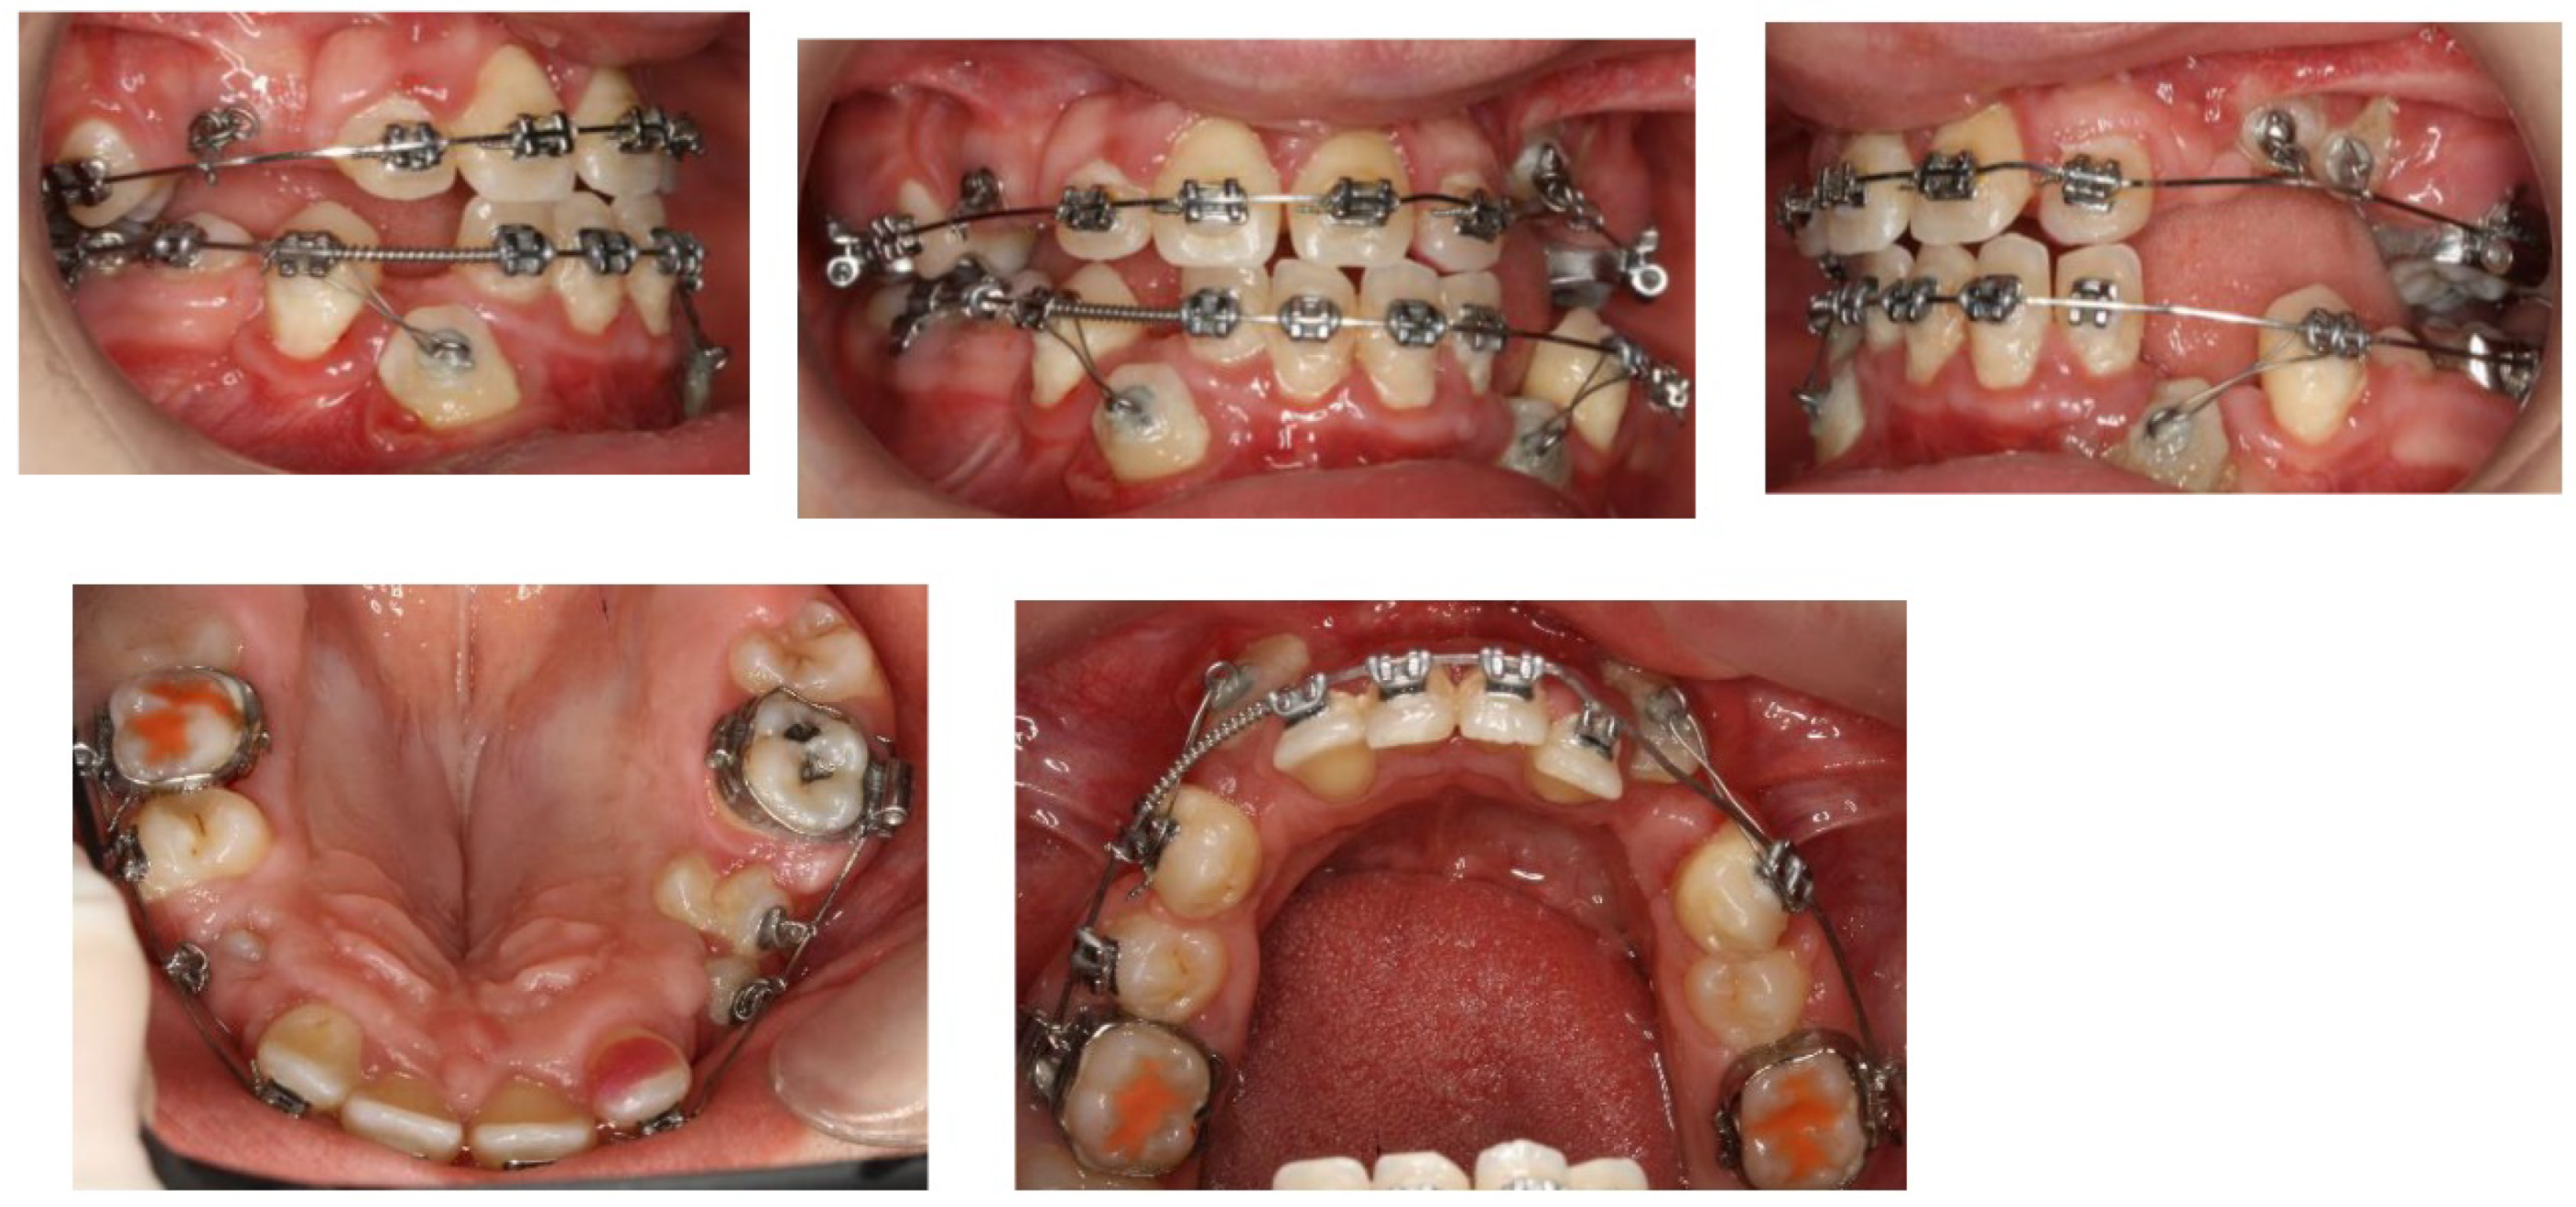

In June 2020, the incisors 22 and 11 were palpable under the vestibular mucosa. In local anesthesia (LA) the patient underwent a surgical exposure of 22 and 11, it was fixed a hook-shaped attachment on both teeth immediately and the incisors were placed under immediate load. (Figure 14). In December 2020 regular orthodontic brackets Roth prescription 018´´ were attached to the surface of 22 and 11.

A follow-up OPG x-ray was taken in January 2021 (Figure 14) . According to the image analysis, the 45 and 35 roots were mature enough and revealed satisfactory activity to erupt spontaneously. Placement of lower fixed appliance followed. Orthodontic bands on the teeth 36 and 46, brackets to the 34, 44 and to the lower incisors, (018´´, prescription Roth) were attached. A space had been forming for the 45 and 35. According to the superimposition of the last two OPG x-rays, the 45 and 35 were erupting spontaneously.

Surgical Intervention 4 (Local Anesthesia)

In January 2022 a surgical exposure in local anesthesia of 33 and 43 was provided, and the attachment was bonded immediately. The canines were encumbered with light distal forces to avoid interference of the canine crowns with the roots of the lower incisors. (Figure 16)

Figure 16. Top 3 pictures : Intraoral photographs after surgical exposure of the lower canines in January 2022. The brackets were bonded immediately, the same as the force loaded. Bottom pictures were taken in January 2024, after surgical exposure of teeth in the upper right and left quadrant in March 2023.